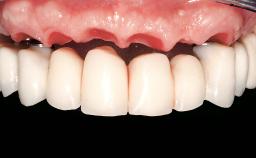

Immediate Loading of Six Implants in the Maxilla and Final Restoration with a Full-Arch Gold/Ceramic FDP Involving the Concept of Tilted Implants

A 61-year-old male patient with a failing fixed maxillary rehabilitation and a fixed mandibular rehabilitation requested a new fixed maxillary rehabilitation. The patient was wearing a temporary metal-reinforced maxillary bridge inserted two years before the consultation. He reported that his previous dentist did not want to insert a definitive framework because he considered the residual teeth to have a negative prognosis. The patient reported a history of recurrent caries and endodontic complications as the main reason for the previous extractions. The anamnesis was negative for periodontal disease and bruxism. The patient’s chief compliant was the mobility of his maxillary prosthesis, which needed to be re-cemented frequently, and discomfort during chewing.Moreover, the patient was not satisfied with the esthetic appearance of his maxillary teeth, which he found too long. The patient asked for a stable and comfortable fixed maxillary rehabilitation and firmly rejected any removable solution.

Prosthesis Type FDP